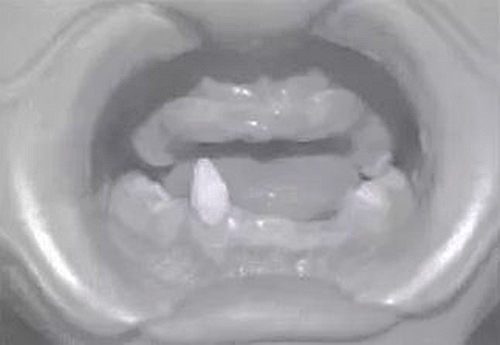

患兒,男,8歲,因“先天缺牙2年.要求鑲牙”于2010年7月就診于我科?;純杭议L(zhǎng)訴孩子牙齒先天發(fā)育不良,無(wú)法咀嚼,擔(dān)心孩子發(fā)育。檢查示:患兒智力正常,頭發(fā)及眉毛稀少,雙側(cè)面部對(duì)稱,囟門(mén)發(fā)育不足,腳趾并攏不全,口內(nèi)查11、12、13、14、15、21、22、23、24、25、31、32、33、34、35、41、42、44、45缺失,75、85為乳牙,43為錐形牙。牙槽嵴較低平,上下牙槽嵴未觸及明顯的骨突及骨尖,無(wú)咬合關(guān)系,頜間距短。雙側(cè)顳下頜關(guān)節(jié)區(qū)無(wú)壓痛、無(wú)關(guān)節(jié)彈響。

圖2患者修復(fù)前口內(nèi)像